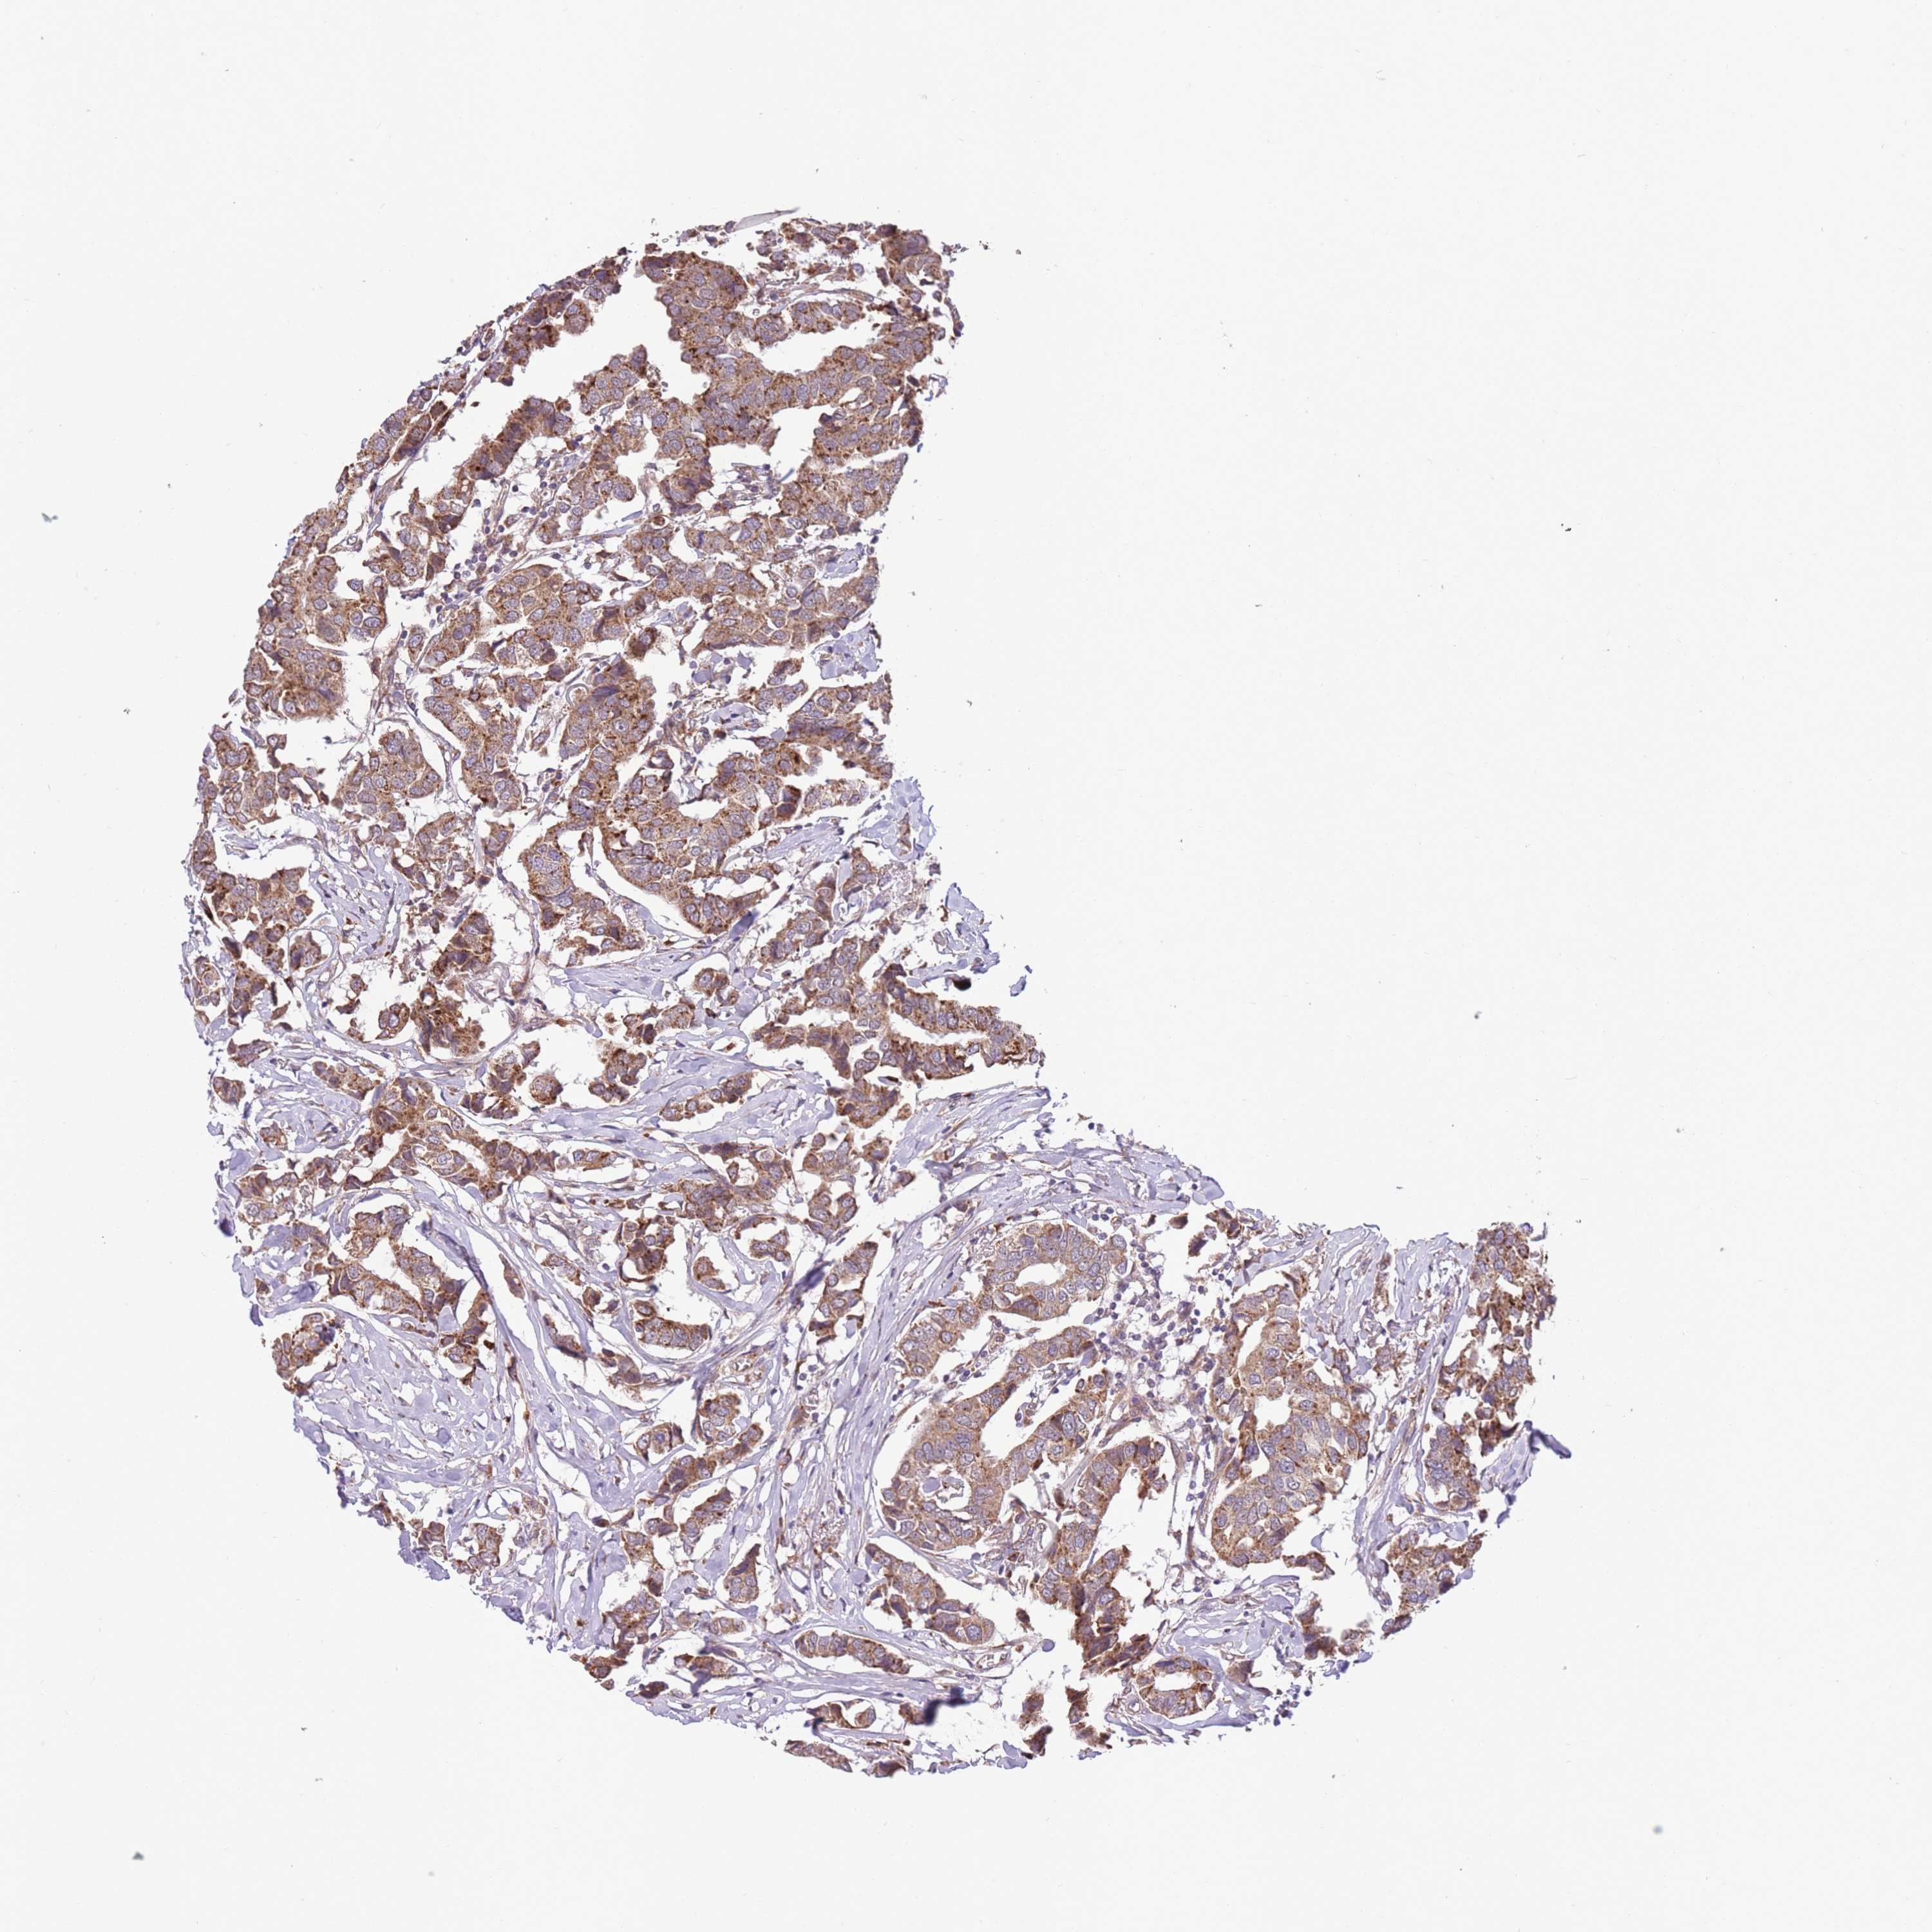

CANCER BREAST CANCER Show tissue menu

BRCA TCGA BRCA VALIDATION PROTEIN EXPRESSION

Breast cancer

Human cancer